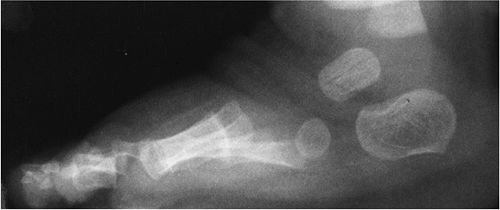

FIGURE 6-34 Oblique radiograph demonstrating the three zones of the proximal fifth metatarsal. There is an ununited Jone’s fracture (arrow) in Zone 2.